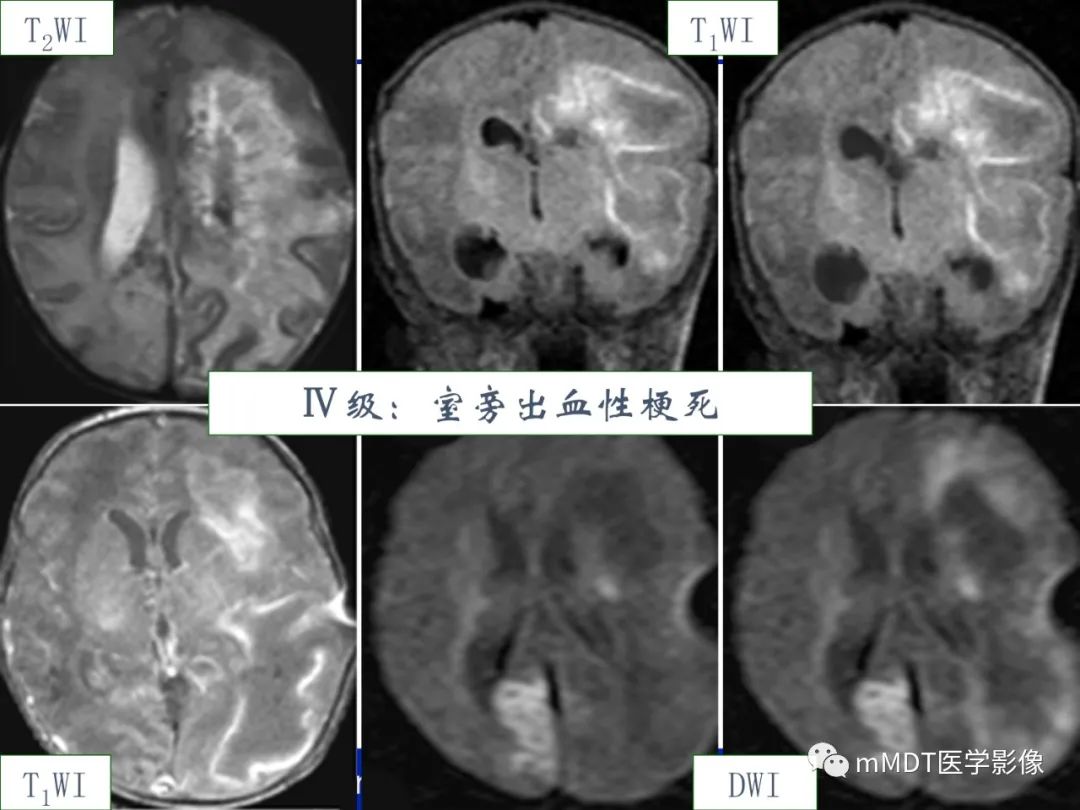

HIE的分度

HIE的严重程度与预后密切相关。

★轻度HIE:一般预后良好,无神经系统的后遗症出现。

★中度及重度HIE:愈后较差,有50%左右的病例复查表现出头颅MRI异常和不同程度的临床表现,25%左右的病例可发展为脑软化和脑萎缩等严重后遗症,并伴有相应的神经系统症状和体征。

早产儿HIE

Ø脑损伤的部位—-脑室周围为主ØØ脑损伤类型、发病机制:

l胚胎生发基质-脑室内出血(germinalmatrix hemorrhage and intraventricular hemorrhages,GMH-IVH)、小脑出血,生发基质未完全退缩、毛细血管的血管壁不成熟,易发生出血;

l脑室旁白质软化(periventricularleukomalacia,PVL),血管的终末段(胎龄越小,髓质穿通动脉发育越差,分支少),缺血易发生白质的坏死。